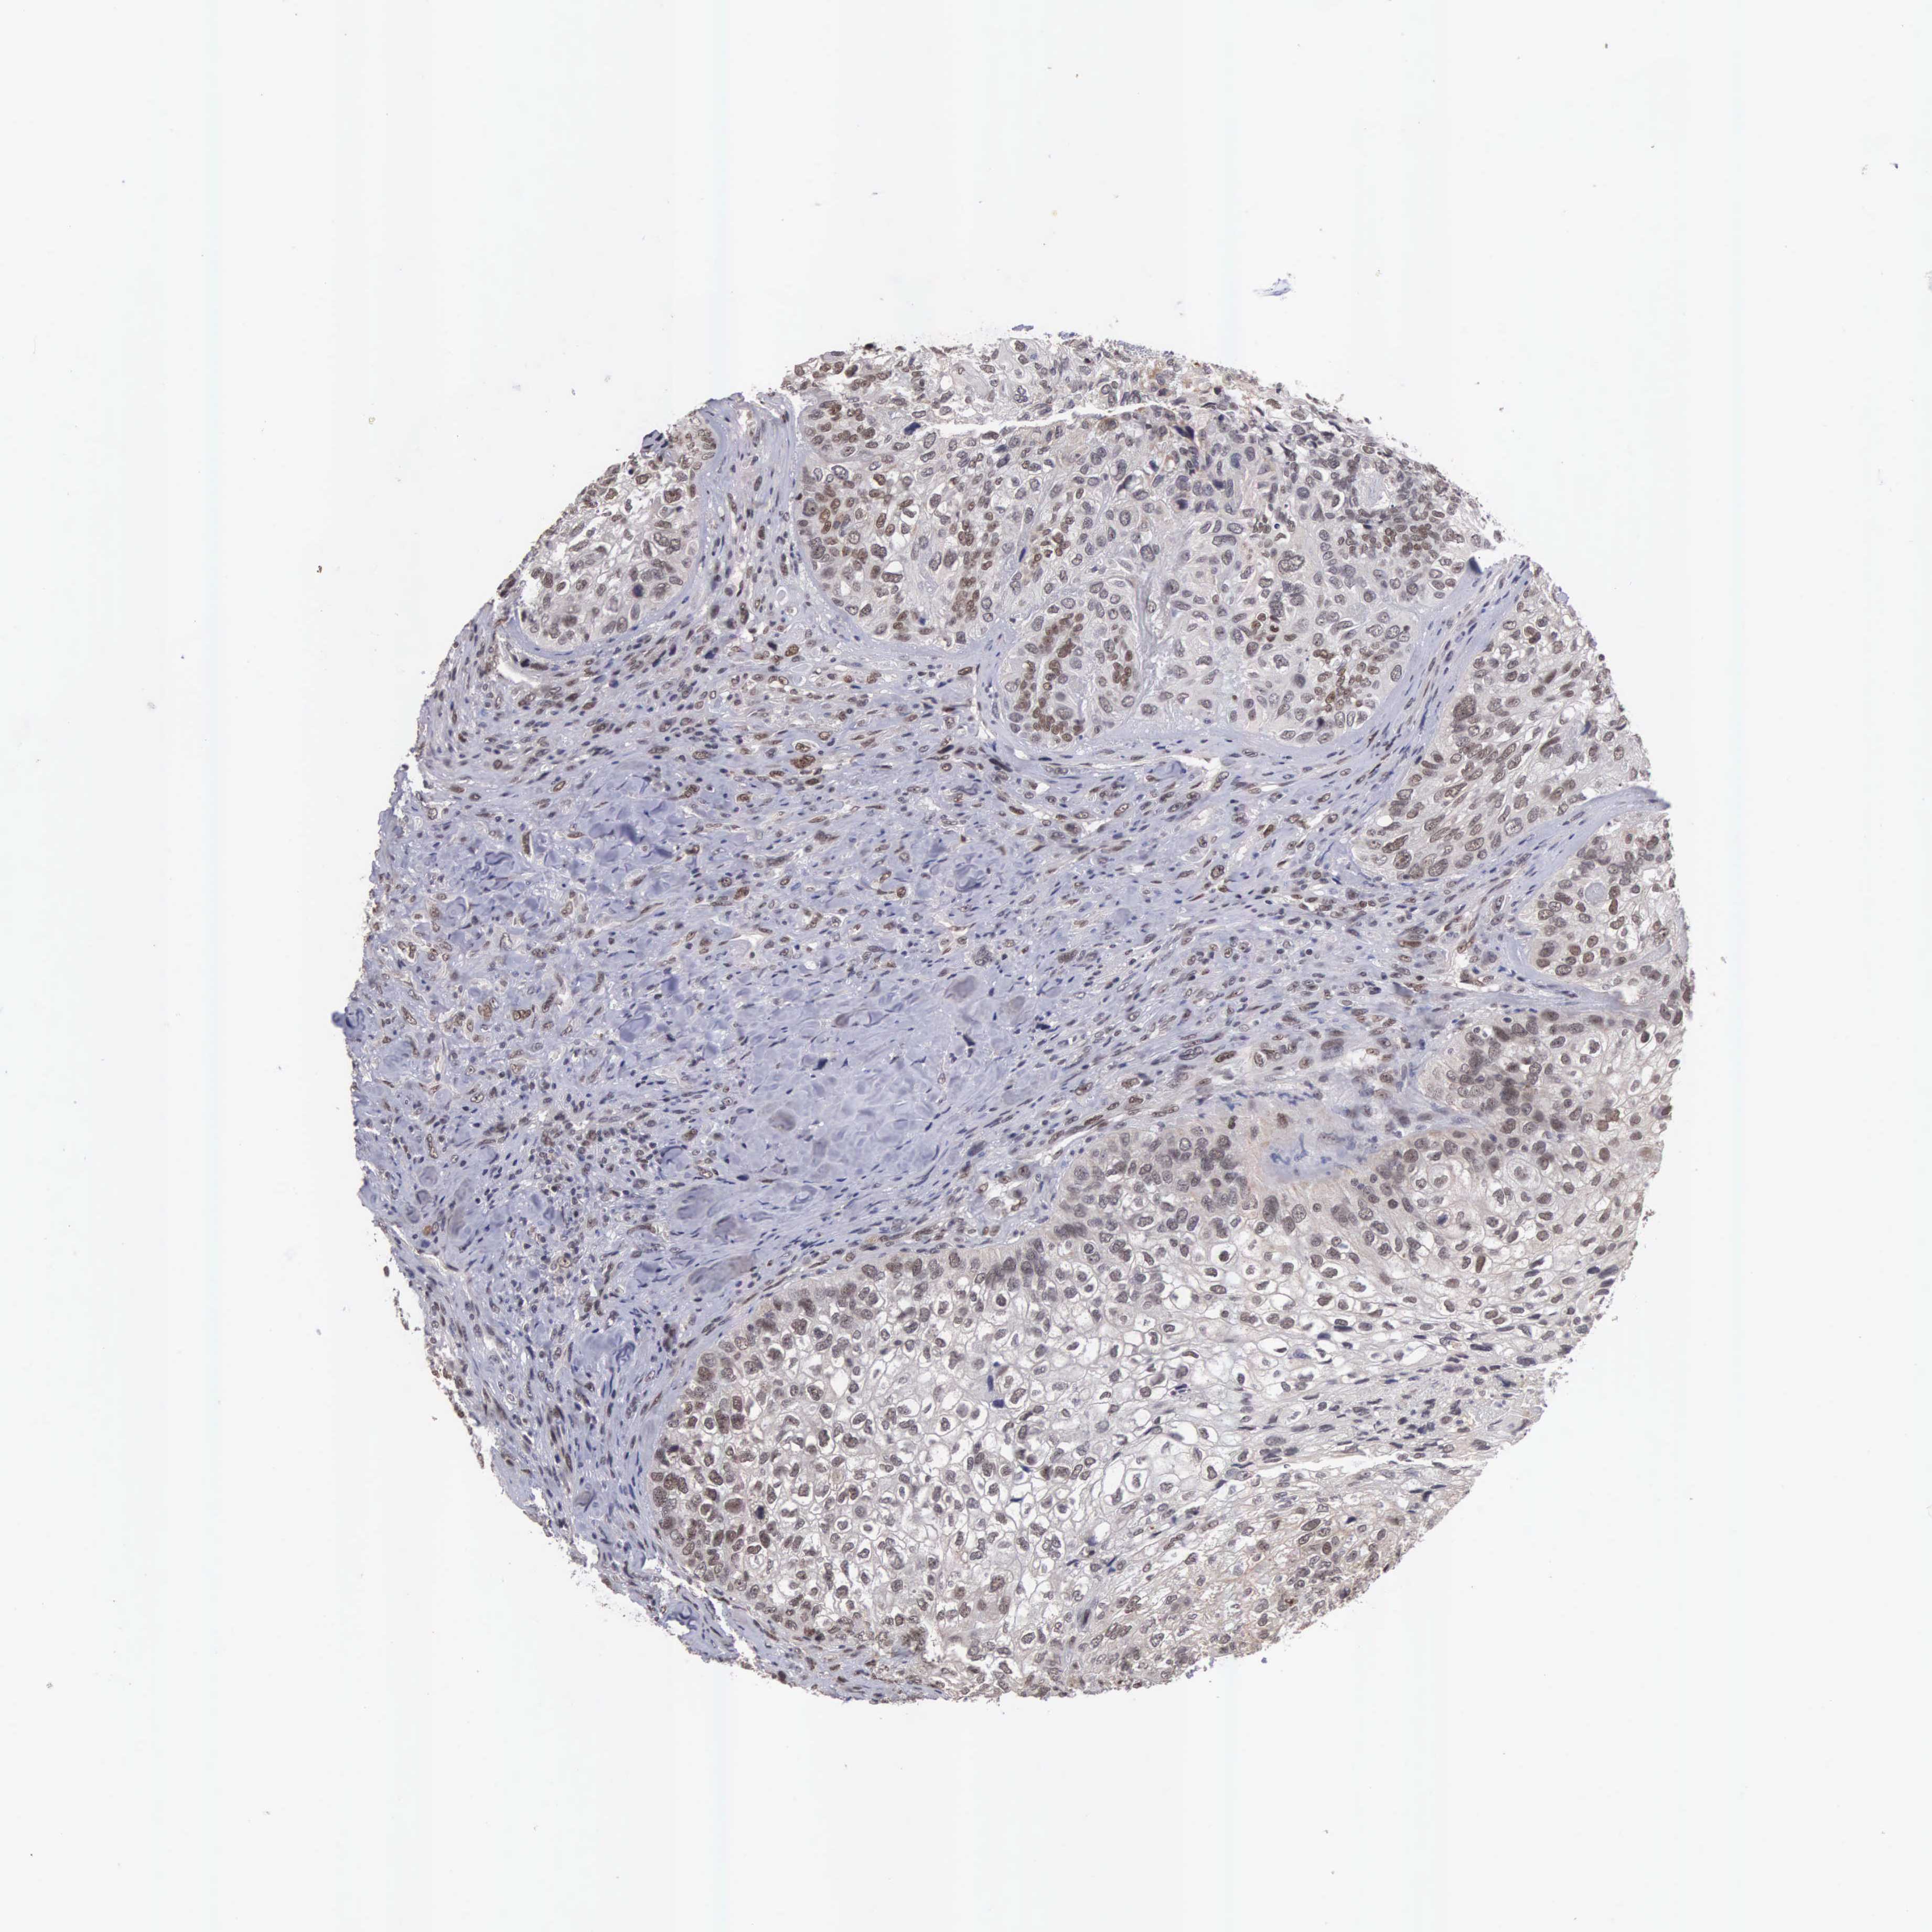

BRCA TCGA BRCA VALIDATION PROTEIN EXPRESSION

ANTIBODIES

AND

VALIDATION